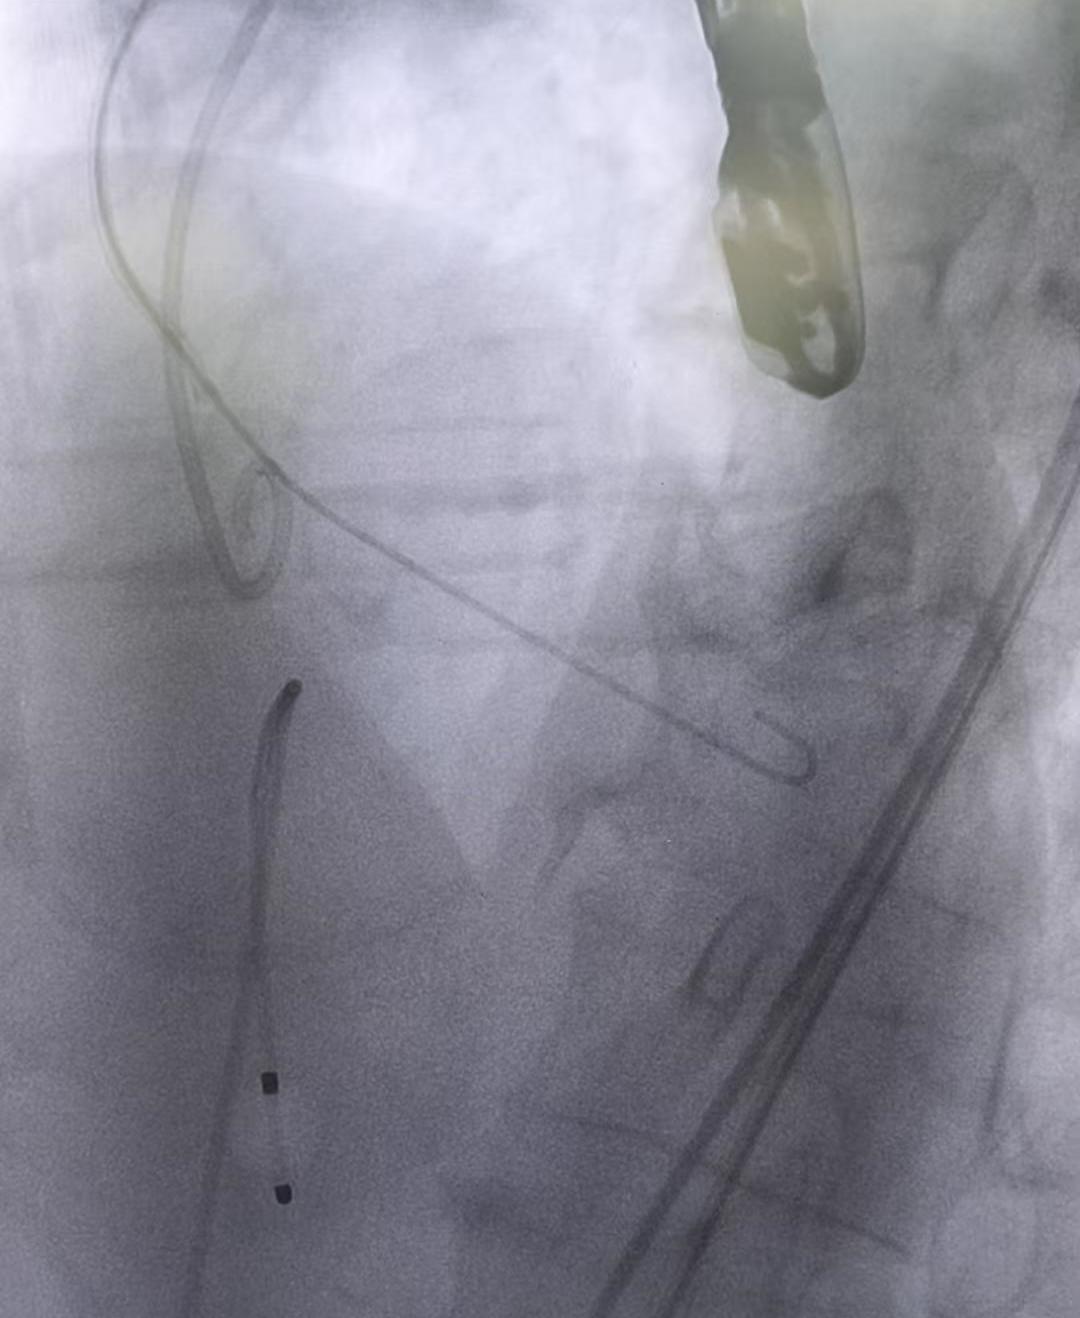

2.“跨弓大鞘”导引鞘就位:

在右股动脉路径准备就绪后,术者将直径22F的“跨弓大鞘”沿着预置导丝送入体内。透视影像显示, 该导引鞘成功穿过曲折的髂动脉和降主动脉,到达了主动脉弓并进入升主动脉内(如上图所示,粗大的 弧形鞘管横跨在主动脉弓区域)。跨弓大鞘特有的弧形结构贴合于主动脉弓的内壁,为手术建立了一条 稳定、宽敞的“隧道”。通过这个隧道,后续的导管和瓣膜输送系统能够在更接近中心轴的位置顺利上 达主动脉瓣区域,大幅降低了曲折解剖对器械推进的影响。